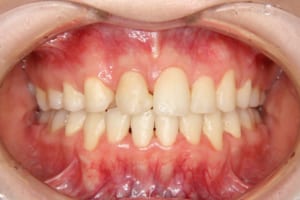

治療後

年齢・性別 19才 女性

主訴 下の歯の凸凹

上の前歯が出ているのが気になる

治療期間 4年6か月

抜歯および非抜歯 上顎:右側中切歯、右側側切歯、左側第一小臼歯

下顎:両側第一小臼歯

費用(保定除く) 889,550円(税込)

その他/備考 上顎右側中切歯および側切歯が、埋伏していた犬歯によって歯根吸収していました。

顎間ゴムも頑張ってくれたが期間がかかりました。

いずれ牽引した犬歯の再度の補綴処置を予定しています。